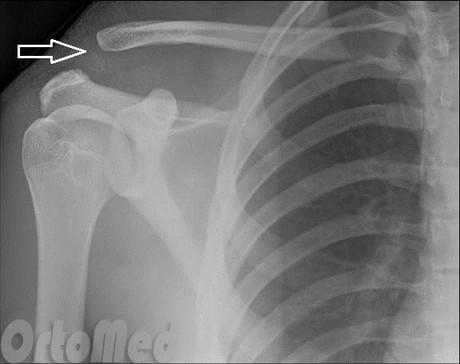

Рис. 1- Разрыв акромиально-ключичного сочленения.

Наиболее распространенная причина вывиха акромиально-ключичного сочленения - это прямое падение на плечо . При таком падении повреждаются связки, окружающие и стабилизирующие акромиально-ключичное сочленение.

Если удар достаточно сильный, происходит разрыв связок, отходящих от нижней стороны ключицы. Это вызывает "разъединение" ключицы и лопатки (рис.1). Лопатка смещается вниз под весом руки, в результате чего появляется "шишка", или бугорок, над плечом.